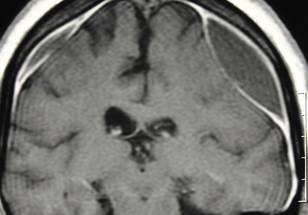

- Chronic subdural hematoma, a pooling of blood between the brain and one of its outer coverings, is one of the most common reasons for neurosurgery and is especially frequent in the elderly because of structural changes in the brain that occur with aging and the increasing use of blood thinners.

A subdural hematoma occurs when there is a tear in one of the thin blood vessels that stretch between the surface of the brain and the overlying membranes that protect the brain. A subdural hematoma can occur because of physical trauma such as a car accident, however, it may also develop slowly in the days or weeks after the injury. This study explored treatment for subacute or chronic subdural hematoma. Subacute subdural hematoma occurs following less severe trauma, such as a concussion – with symptoms such as weakness, numbness, tingling, seizure, headache, confusion or dizziness that develops over hours or days after the event. Chronic subdural hematoma can result from slow bleeding after minimal trauma that the patient may not even remember – symptoms may be subtle and/or may take weeks to be noticeable enough to seek treatment.

“Chronic subdural hematoma is one of the most common neurosurgical conditions and is likely to increase in the future since we have a sizeable aging population, with many taking blood thinners to manage various medical conditions,” said study co-author Jason Davies, M.D., Ph.D., an associate professor in the departments of neurosurgery and biomedical informatics at the State University of New York, Buffalo. “These hematomas often form in the elderly because as we age, the brain shrinks and pulls away from the inside of the skull, stretching the veins that form a bridge between the dura and the brain, which makes them more likely to tear after a small trauma and leak blood into the protective space between the brain and skull, the dura.”